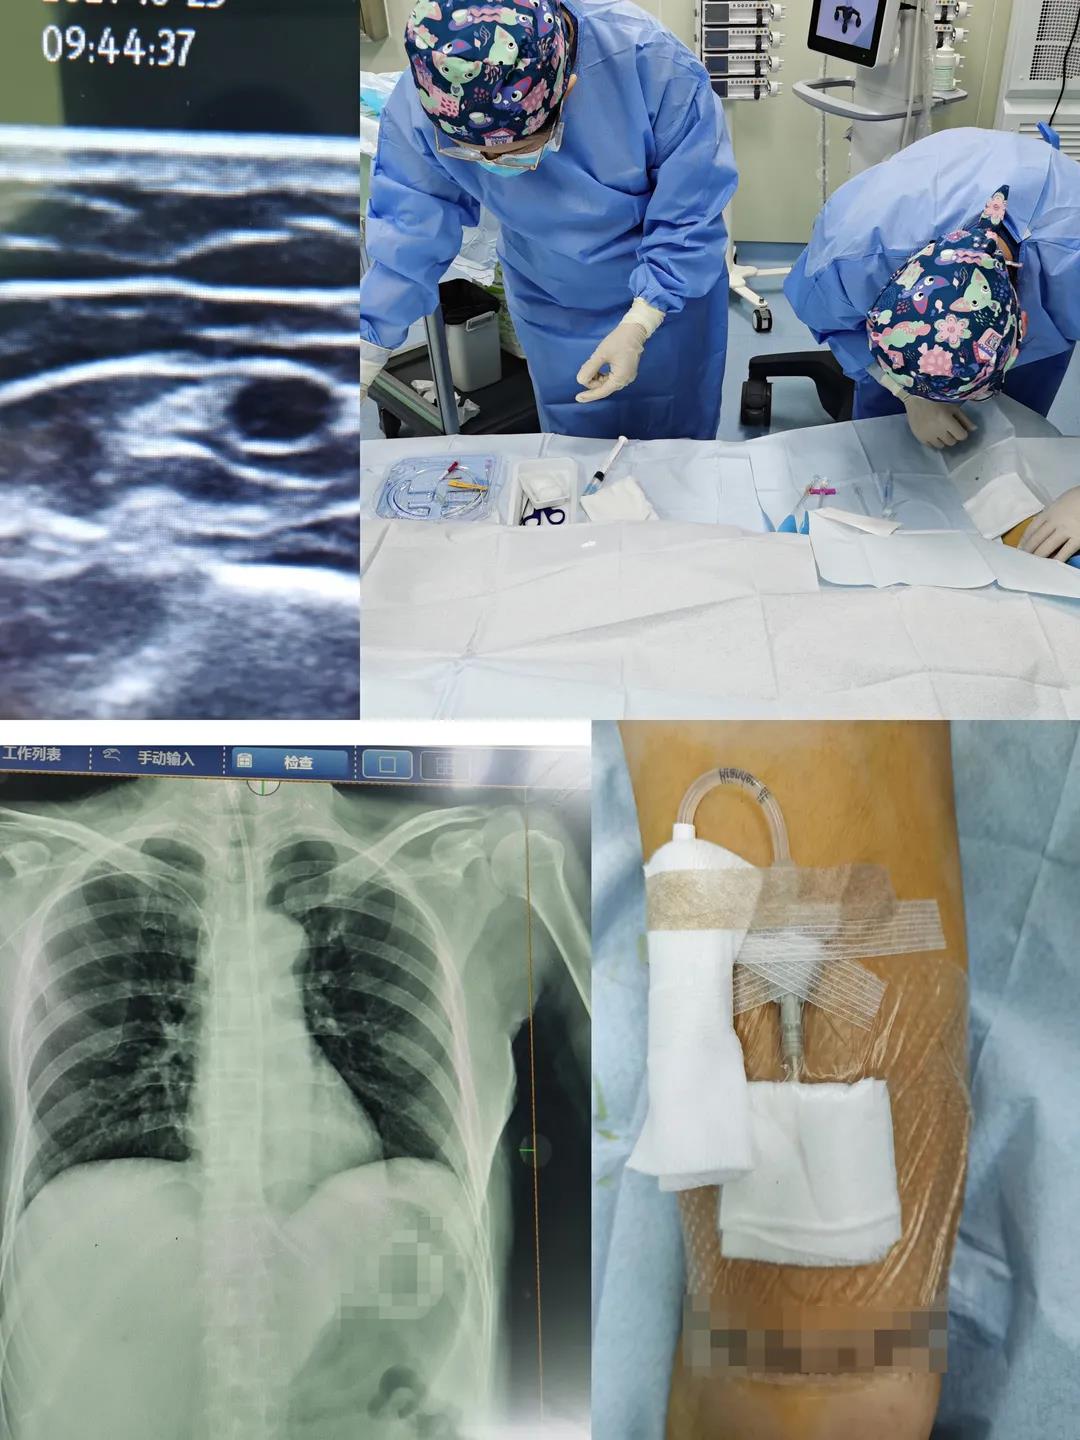

近日,新生儿科开展我院首例新生儿胸腔穿刺成功救治危重患儿,家属送锦旗深表感谢!

“感谢中医院妇科全体医护人员,你们快速、有效的抢救帮我捡回了一条命!”患者刘某在为妇科送上锦旗时激动万分地说。原来刘某在办理入院手续时,突然出现下腹部剧烈疼痛、心慌、恶心及呕吐。妇科主任刘娜、景瑞副主任医师和米娟主治医师立即组成抢救团队迅速展开紧急救治,从患者出现症状到脱离危险仅用时50分钟,为妇科团队点赞!

重症医学科护士长王婷婷在B超引导下为普外科患者行右侧贵要静脉PICC置管术,为急危重症患者提供安全可靠的静脉通路,减少了不必要的穿刺,极大降低了导管相关血流感染的风险,为患者提供高效优质的护理服务,我们一直在行动……